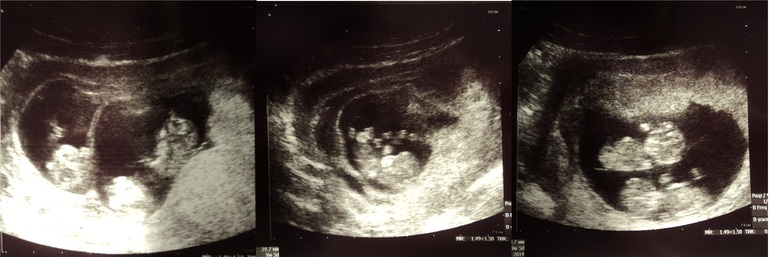

На фото :1-все трое ,2-одна Танюшка и 3-близняшки Аня и Маша

Вопросы о беременных и для беременных двойнейНашлась минутка и я решила поделиться воспоминаниями о своей ,еще недавно прошедшей беременности.Все так быстро проходит и мелочи забываются. Так получилось,что забеременеть с мужем мы не могли больше 7 лет.Естественно прошли обследования(не один раз),и все таки остановились на попытке ЭКО.Насобирали денег и вперед!!!Подсадили мне две яйцеклетки.Мы очень хотели двойняшек.А в 10 недель на первом скрининге врач говорит:"А вы знаете,что у вас тройня???"Мы просто были в шоке!!На вопрос оставим или нет мы однозначно ответили -конечно да!!Когда я увидела на экране этих 10недельных крошек,шевелящих ручками и ножками,в голове не укладывалось,как можно сделать редукцию.